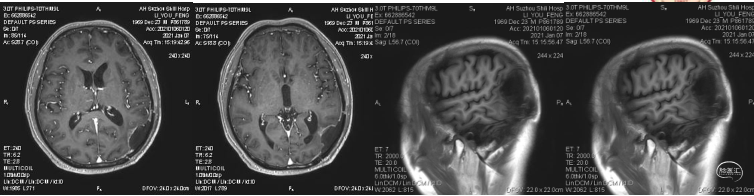

患者为中年男性,因“间断性头痛2月,加重1周”于2020年4月30日入院。入院时神经系统体征(-)。术前诊断为左顶枕叶胶质瘤。